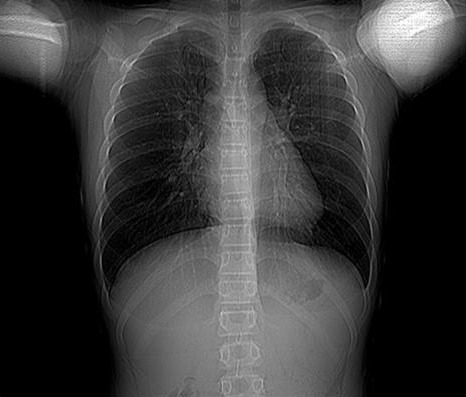

WIth the events happening around the world due to the global pandemic, I came up with this idea to build a covid detector based on XRAY images. Because SARS-CoV-2 attacks the epithelial cells lining the lungs, it can be detected from posterioranterior view of the lungs. With limited testing kits, this solution can prove to be favorable and also give results in an instant.

Trained a ML model to classify xray images of lungs as covid positive or negative and exposed web sevice using flask